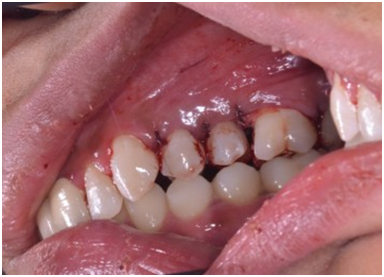

A 22-year old female patient presented in our private dental practice set up with complaint of pain, food stagnation, foul smell and loosening of couple of teeth in upper jaw. Intraoral examination revealed vertical bone loss around distal surface of upper right second premolar and mesial surface of first molar (Figure 1). The pocket depth was measured to be more than 15mm (Figure 2). The severely affected premolar and molar, on pulp testing showed pulpal involvement leading to diagnosis of endo-periodontal lesion.

After 4 weeks, surgical intervention was carried out. Under local anesthesia a full thickness mucoperiosteal flap was reflected to entirely expose the underlying bony defect (Figure 3). Scaling and root planing was again carried out with osteoplasty to make sure the site becomes clean and non-infected. Freeze-dried bone allograft (surreoss) 0.5cc powder was condensed into the bone defect (Figure 4) and 1x2cm Acellular Dermal Matrix Membrane (Surederm) was placed over the graft area to prevent the epithelial cell migration (Figure 5). Finally, interrupted silk (4/0) suture were placed to approximate the soft tissue (Figure 6). Post-operative instructions were given and patient was directed to use chlorhexidine gel and rinse three times for a period of 15 days and suitable antibiotics were prescribed for five days. As the prognosis of tooth was highly questionable patient was recalled on follow up after 1 week, 2 weeks and 4 weeks. After 3-months’ patient’s intraoral radiograph showed remarkable improvement in regard to bone repair and patient’s satisfaction (Figure 7). Clinical evaluation on 3-month, 2-year and 5-year recall exhibited marked reduction in pocket depth up to 12mm with radiographic evidence of further hard tissue repair (Figure 8). A 5-year recall showed a stable probing depth of 3 mm with functionally standing in her oral cavity despite the fact that she refused to have a crown on the treated tooth (Figure 9).